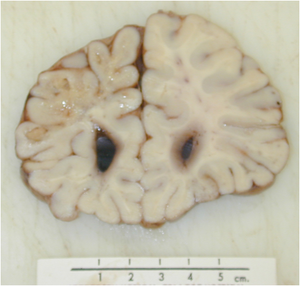

A 68 year old woman begins having phone conversations with “God”. Additionally she is forgetting where she put various objects her house. Based on her symptomatology and the brain specimen below, what is her diagnosis?

Dementia with Lewy bodies:

Early dementia, hallucinations, cognitive fluctuations